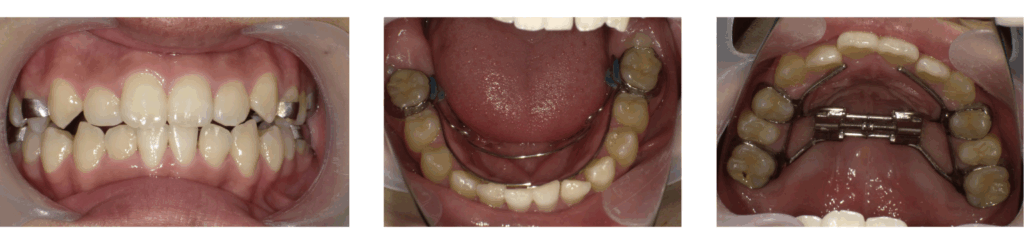

治療後

症例2:急速拡大装置のみ使用した症例

装置装着

拡大完了